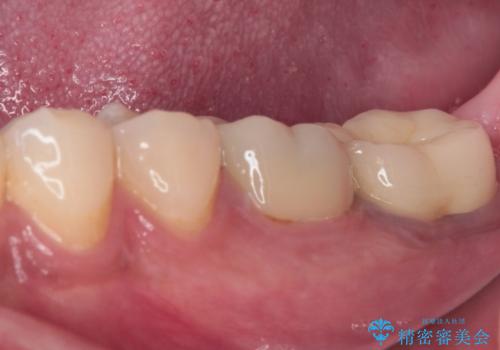

- 間もなく海外赴任という状況で奥歯のクラウンが割れてしまったとのことで来院された患者様です。

下顎の1番奥の歯であり、歯肉に覆われている部分が大きいためセラミックの十分な厚みが取れない状態でした。

強化セラミックを用いたオールセラミッククラウンにて補綴治療を行うこととしました。

十分な土台の高さを確保できない状態であったので、維持力のある土台の形態に整えることで、極力長持ちする治療を心がけました。